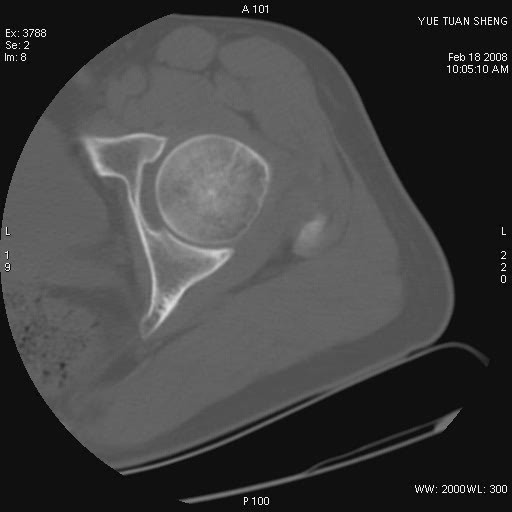

患者,男,56岁,左髋部疼痛1个月,x线:左股骨头高密度影,性质待定,右侧正常。左髋ct如图

左股骨颈区椭圆形磨玻璃样影,边缘明显硬化环环绕,其内见斑点状类钙化高密度影考虑 良性骨病-----骨纤,骨化性纤维瘤,内生软骨瘤。